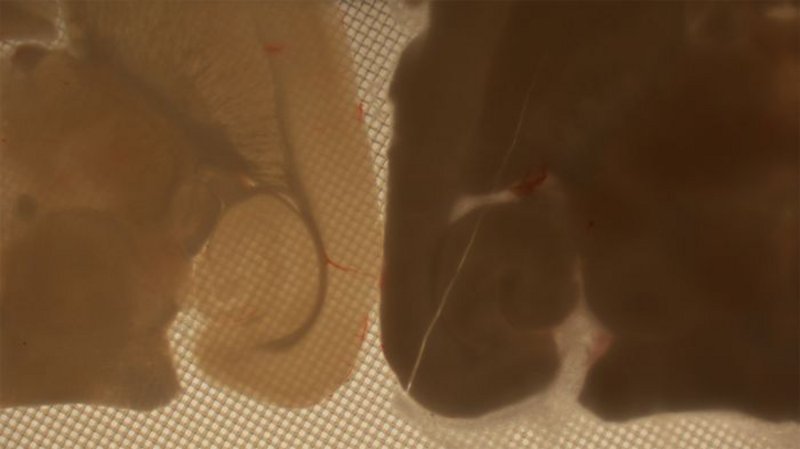

Das Team hat den Erfolg seiner Methode an Hirnschnitten erprobt. Zudem kühlten die Beteiligten auf diese Weise auch eine komplette Hirnstruktur des Nagers auf -130 Grad herunter, den Hippocampus. Dieser spielt bei der Speicherung von Gedächtnisinhalten eine wichtige Rolle. „Wir konnten mit Elektronenmikroskopie-Aufnahmen nachweisen, dass die Nanostruktur des Gewebes sich durch den Einfrier-Vorgang nicht veränderte“, sagt German. „Nach dem Auftauen bildeten sich im Hippocampus zudem wieder spontan elektrische Signale, die sich ganz normal über die neuronalen Netzwerke fortpflanzten.“